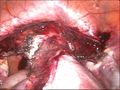

استئصال الرحم من البطن

أما في حالة استئصال الرحم من خلال البطن يقوم الطبيب بعمل فتحة كبيرة في البطن لاخراج الرحم، ويكون الفتح كبير ليساعد الجراح على الوصول لكل أجهزة منطقة الحوض، وتساعد هذه التقنية الطبيب ليقوم بإجراء عملية استئصال الرحم الكلي، كما يمكن ان يقوم أيضا بإزالة المبيض والأجهزة الأخرى.

ومن أسباب عملية ازالة الرحم من خلال البطن: يحتاج الطبيب إلى اجراء عملية استئصال الرحم من البطن للعديد من الاسباب منها:

– في حالة اذا كان الرحم كبير.

– في حالة اذا كان حجم الأورام الليفية أكبر من 20 سم – اذا كان الجزء المطلوب استئصاله من الرحم يوجد حوله الأوعية الدموية.

– في حالة الاصابة بسرطان عنق الرحم، أو الرحم، أو سرطان المبايض.

– اذا كانت كتلة المبيض كبيرة الحجم.

– الندوب والبطانة المهاجرة في منطقة الرحم والحوض.